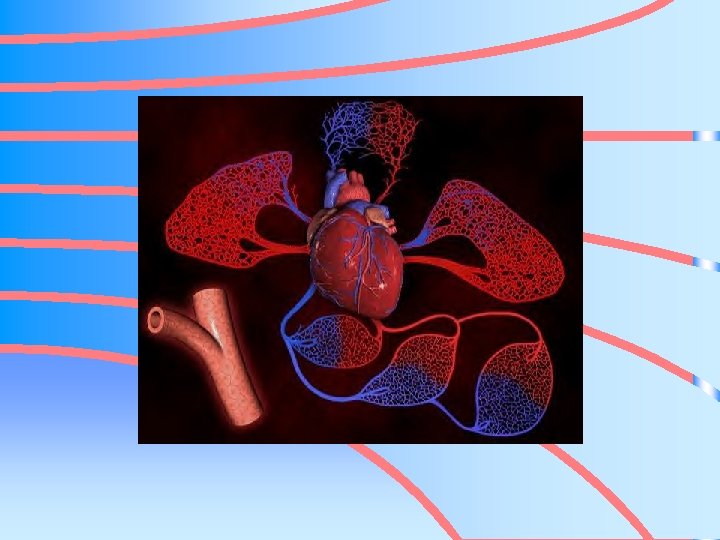

CARDIOVASCULAR SYSTEM • ALSO KNOW AS CIRCULATORY SYSTEM

CV SYSTEM • HEART • BLOOD VESSELS • BLOOD

TRANSPORTATION SYSTEM • TRANSPORTS – OXYGEN – NUTRIENTS TO BODY CELLS – CARBON DIOXIDE – METABOLIC MATERIALS AWAY FROM BODY CELLS